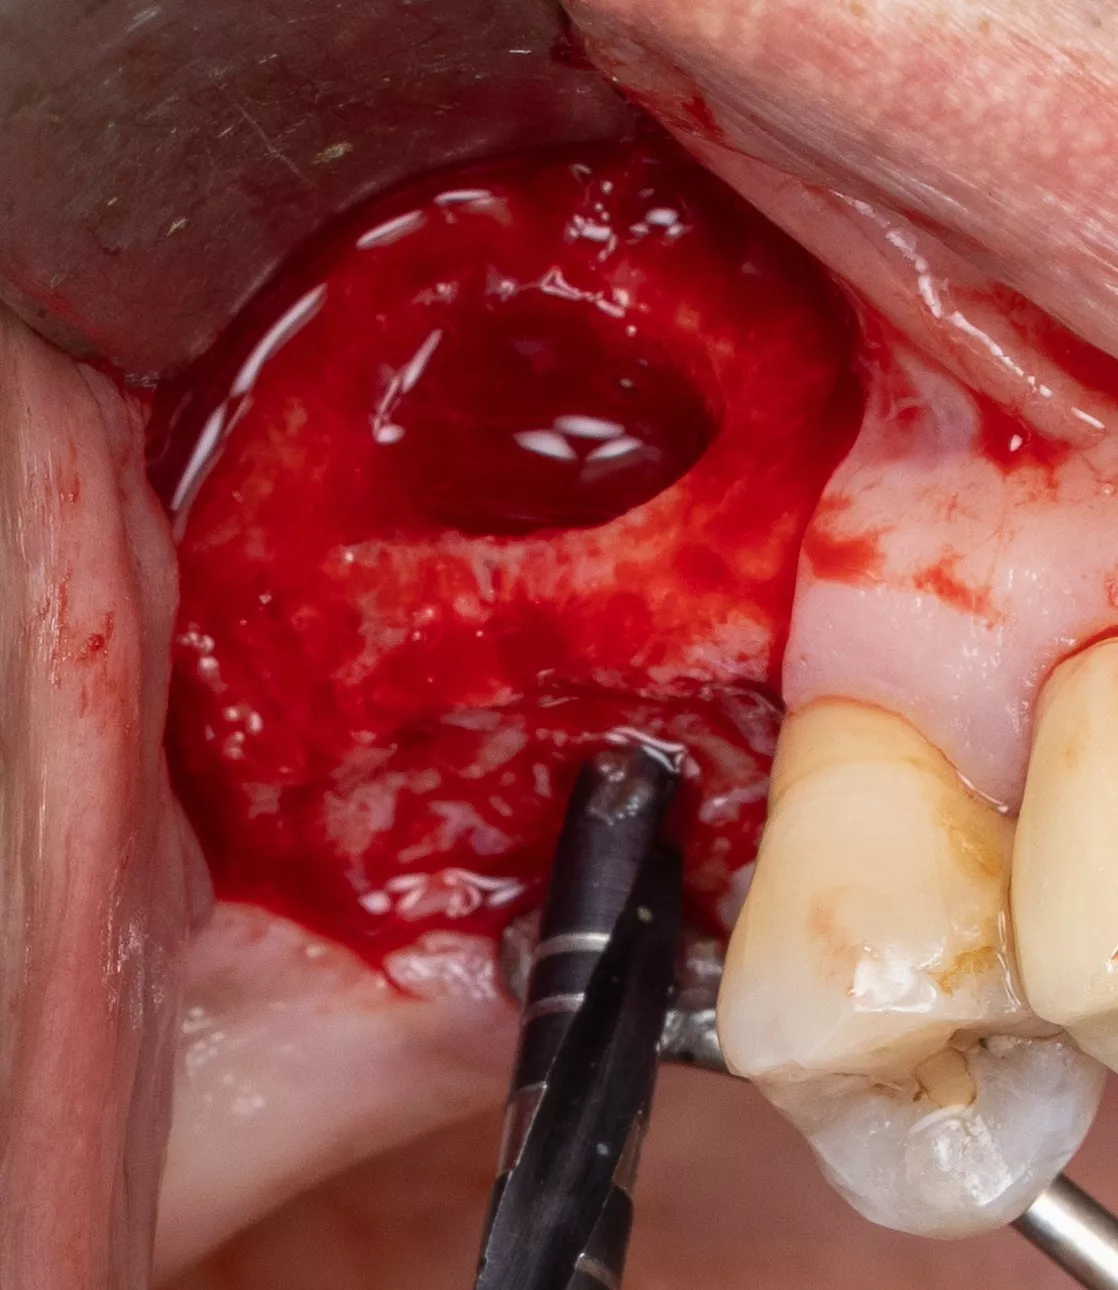

4. Sinus window : Subtractive osteotomy without preservation of the bone flap using a 2.5 mm diamond bur mounted on a surgical handpiece. The Schneiderian membrane (sinus mucosa) of slightly bluish grey color is exposed.

5. Initiation of lifting of the sinus mucosa through the inferior mesial window angle.